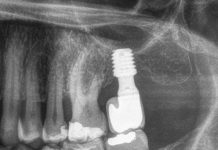

Per ciascun impianto, al momento del posizionamento e in occasione di ciascuno dei controlli programmati (a 12, 24, 36, 48 e 60 mesi rispettivamente, ove possibile), erano realizzate radiografie endorali peri-apicali con centratore di Rinn (Rinn®, Dentsply, Elgin, IL, USA).

Le radiografie erano in primo luogo analizzate per escludere la presenza di eventuale radiotrasparenza peri-implantare, segno evidente di peri-implantite o patologia da sovraccarico e, secondariamente, per poter misurare la distanza tra la spalla dell’impianto e il primo contatto osseo visibile (distance between the implant shoulder and the first visible bone contact, DIB) in mm, nei siti mesiale e distale all’impianto38-40.

Grazie a questa valutazione, infatti, era possibile registrare eventuali modificazioni nella dimensione verticale dell’osso intorno all’impianto e procedere a una valutazione della stabilità del tessuto osseo peri-implantare nel corso del tempo. Per potere correggere eventuali distorsioni dimensionali dovute alla radiografia, la lunghezza apparente (misurata direttamente sulla radiografia) veniva comparata alla reale lunghezza dell’impianto, già nota, introducendo la seguente proporzione:

Lunghezza impianto misurato sulla radiografia: Lunghezza impianto reale (nota) = Difetto misurato sulla radiografia: Difetto reale (incognita)

attraverso la quale era possibile stabilire, con discreta precisione, l’eventuale entità della perdita ossea verticale attorno all’impianto, nei due siti di misurazione41.